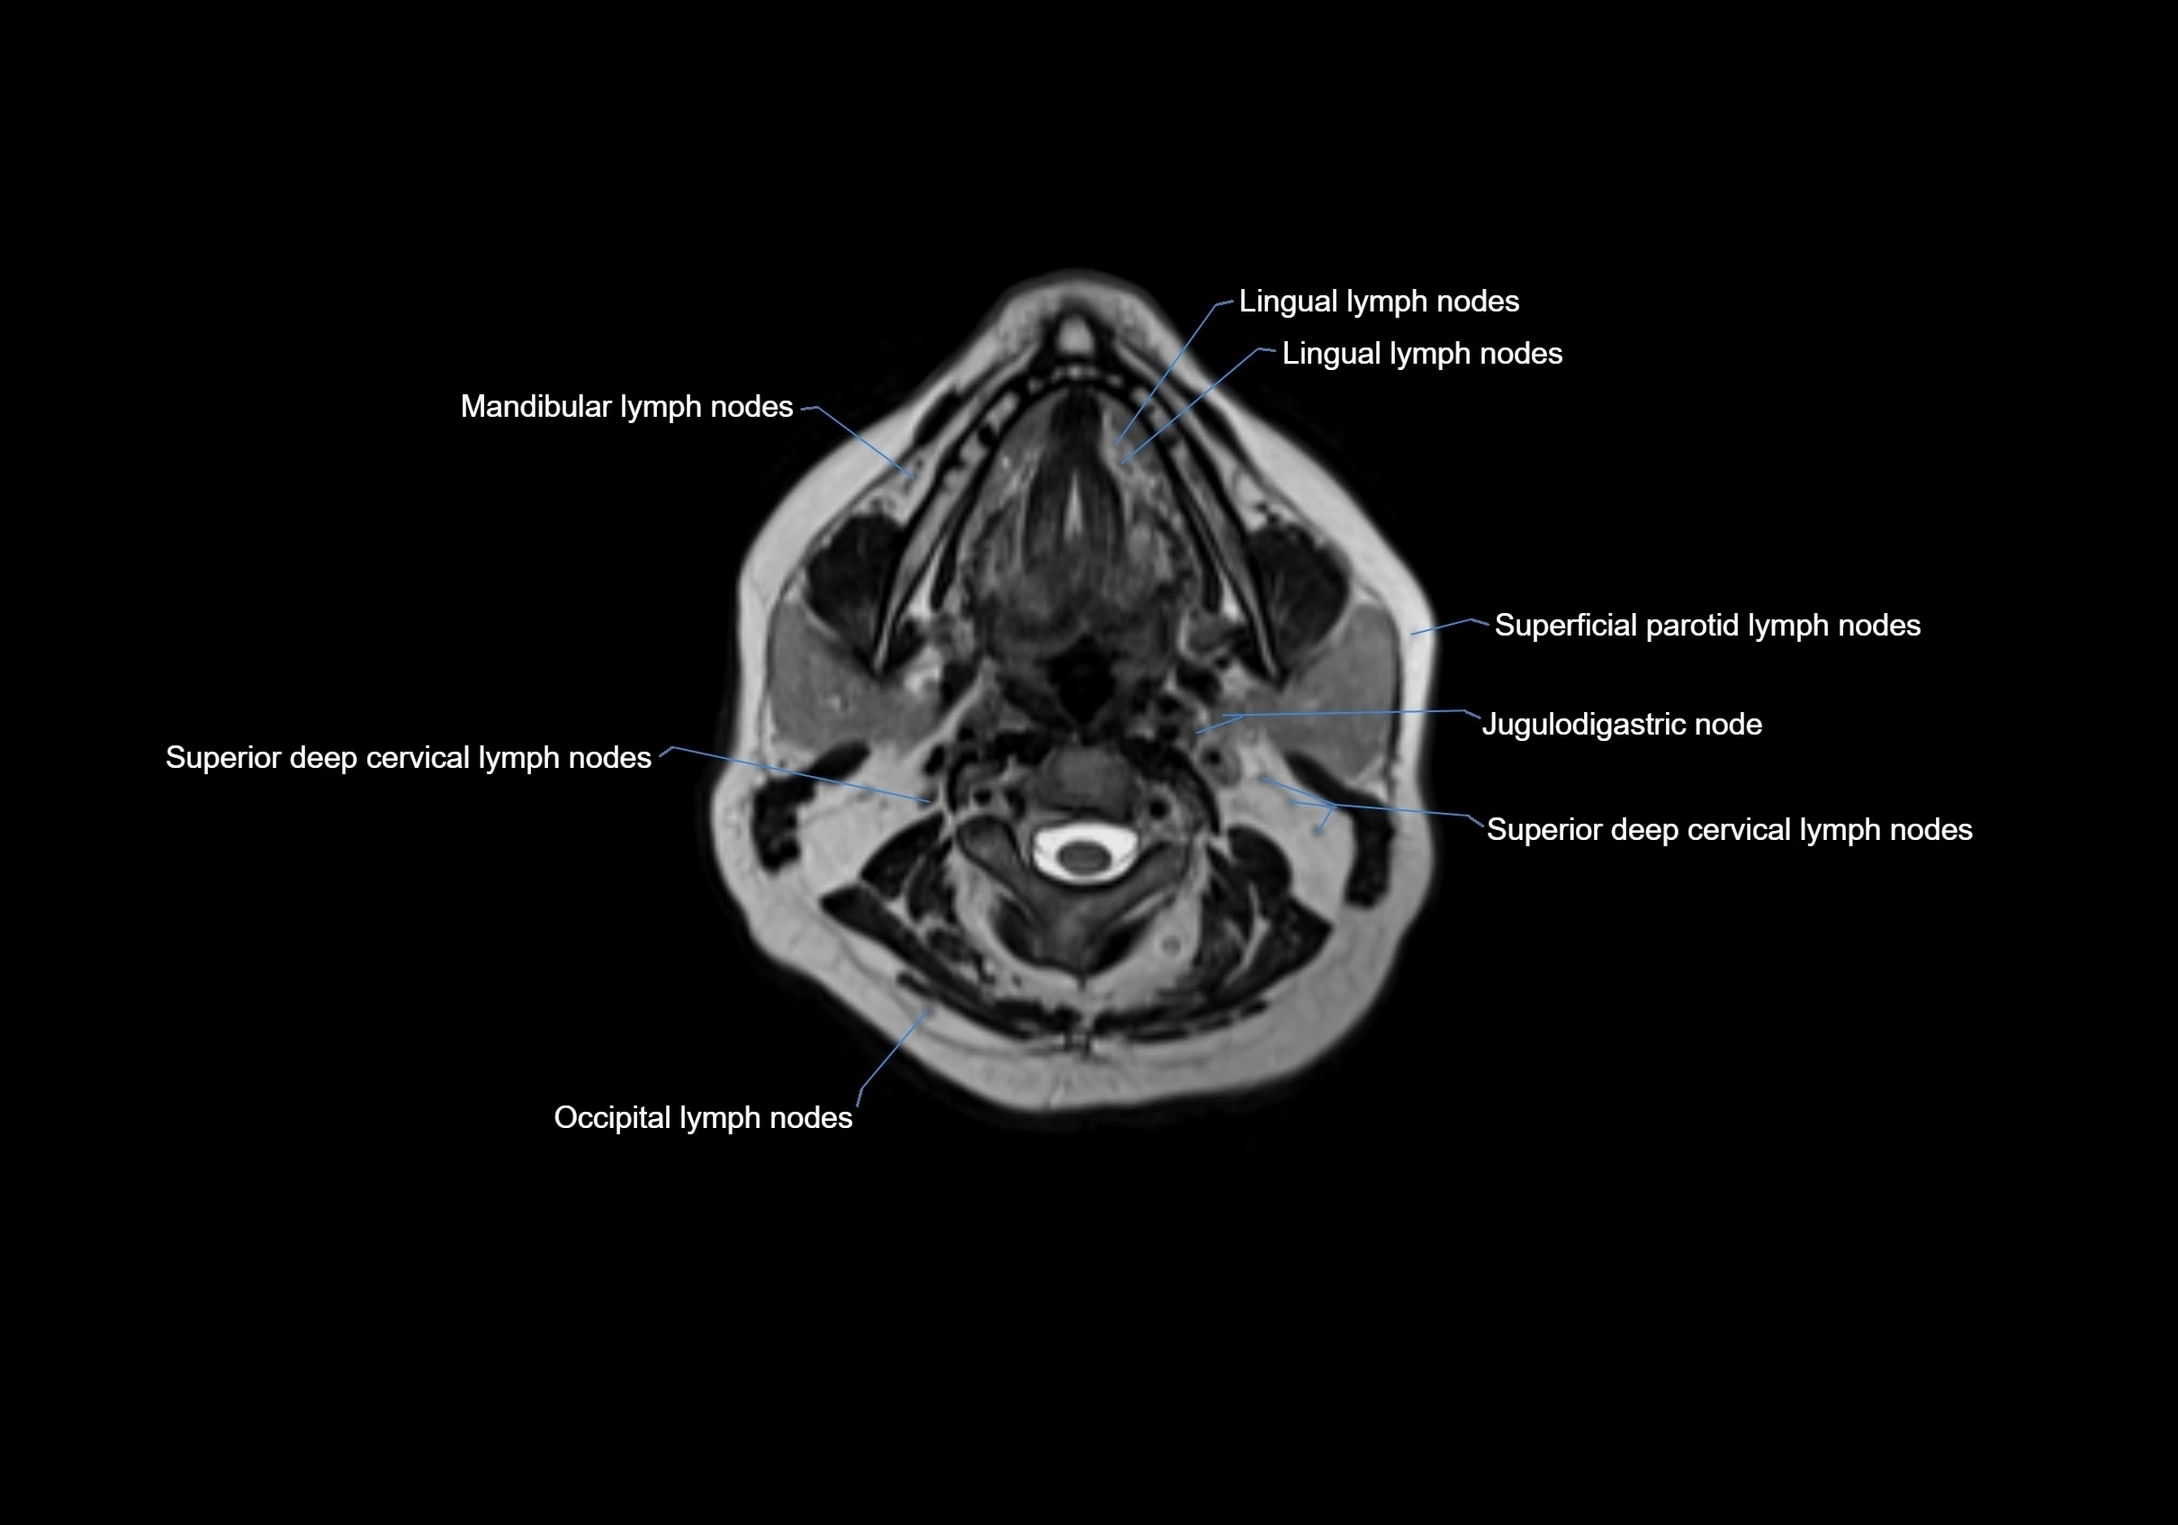

Accessory lymph nodes are small, secondary lymph nodes located along the main facial and cervical lymphatic chains, often adjacent to primary lymph nodes, such as preauricular, submandibular, or occipital nodes. They are typically less than 5 mm in diameter, embedded within subcutaneous fat or connective tissue, and may be variable in number and location. These nodes provide additional filtration and immune surveillance for lymph collected from the face, scalp, and neck regions. Accessory lymph nodes are usually non-palpable in healthy individuals but may enlarge in response to infection, inflammation, or metastasis, making them clinically significant.

Location

• Found along primary lymph node chains, including preauricular, submandibular, parotid, and occipital regions

• Embedded in subcutaneous fat or superficial fascia, often lateral or posterior to primary nodes

• Variable in number; may occur unilaterally or bilaterally, depending on individual anatomy

MRI images

image